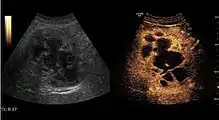

2D ultrasound, Doppler ultrasound and especially CEUS can play an important role in pretherapeutic staging, particularly when sectional imaging investigations (CT, MRI) provide uncertain results or are contraindicated. During the interventional procedure, ultrasound allows guidance of the needle into the tumor. CEUS allows guidance in areas of viable tissue and avoids intratumoral necrotic areas. CEUS also allows assessment of therapeutic effect immediately post-procedure (with the possibility of reintervention in case of partial response) . To accurately assess the effectiveness of treatment it is mandatory to compare the tumor diameter before therapy with the ablation area. The volume of damaged tissue must be higher than the initial tumor volume. CEUS appearance is that of central nonenhanced area showing a peripheral homogeneous hyperenhanced rim due to post-procedure inflammation. 24 hours after the procedure the inflammatory peripheral rim is thinning and the necrotic area appears larger than at the previous examination. Thus, a possible residual tumor may appear more evident. Residual tumor has poorly defined edges, irregular shape, and the tumor diameter is unchanged. Residual tumor tissue is evidenced at the periphery of the tumor as an eccentric area behaving as the original tumor at CEUS examination, with arterial hyperenhancement and portal and late wash-out. Ultrasound examination 24 hours after the procedure, including CEUS, can show apart from the character of the lesion any potential post-intervention complications (e.g. active bleeding).

Local recurrence is defined as recurrence of a hyperenhanced area at tumor periphery in the arterial phase, with portal and late wash-out. Sometimes, especially for HCC treated by alcoholization (PEI) hyperenhanced septa or vessels can be shown inside the lesion.